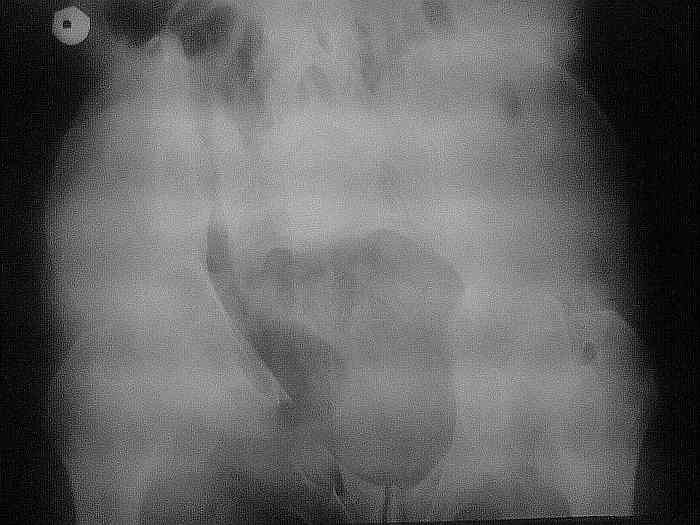

Застарелое повреждение таза

Ситуация такая. Мужчина 50 лет, невысокий, худой. Перелом костей таза пять месяцев назад. Пришел на костылях. В поисках адекватной помощи в краевых больницах был "переадресован" не ближе чем как в Курган и Москву.

Денех естессно нет + семейные неурядицы в связи с приобретением статуса инвалида. Ехать, после хождений по мукам, теперь никуда не хочет. Готов на оперативное лечение в нашем отделении. Больной стабильный. Неврологического дефицита нет. Функции тазовых органов в норме.

Проблема: У нас нет опыта в оперативном ведении таких больных, но есть желание, головы и руки.

Вопрос: Если у нас шанс прооперировать такого больного в наших условиях с помощью нашего многоуважаемого виртуального сообщества? Например, определения тактики, вида вмешательства, последовательности манипуляций, технических тонкостей и определения "подводных камней"? И т.д. и т.п.

Тех. оснашение: Есть в наличии детали от набора аппарата Илизарова для лечения переломов таза, винты Шанца (спасибо Челнокову А.Н., наделали их в достаточном количестве :))), длинные канюлированные винты (но не со сплошной нарезкой), рекон. пластины, "Арман" в операционной.

Обрисованы только общие черты проблемы для оценки ситуации. Снимки в аттаче. Кто и что думает по этому поводу?